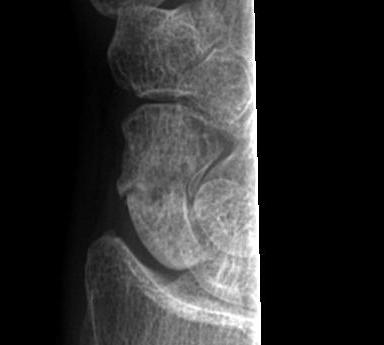

Xray

Sclerotic margins / no sign of healing

Humpback deformity

Look for signs of AVN